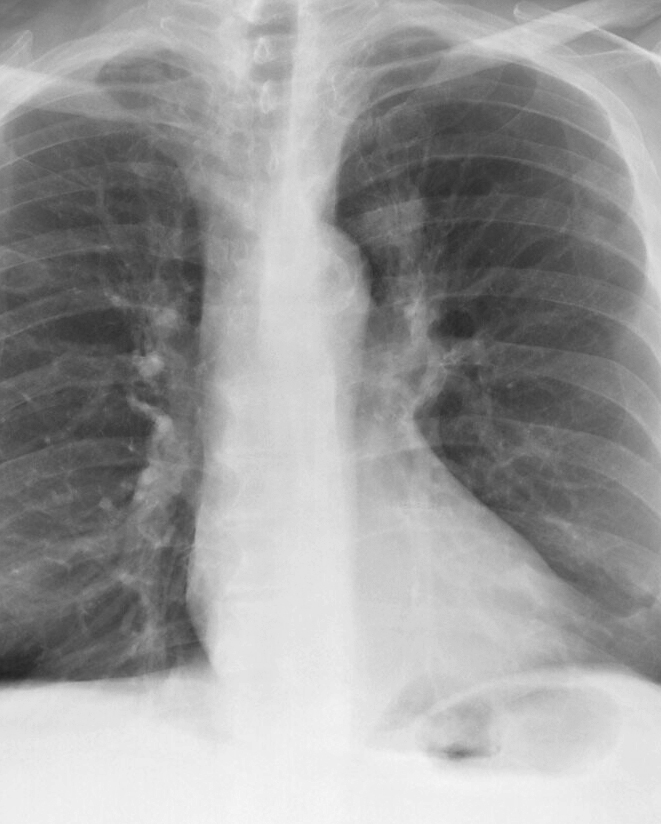

Lung Cancer

Nodules & Masses

8a